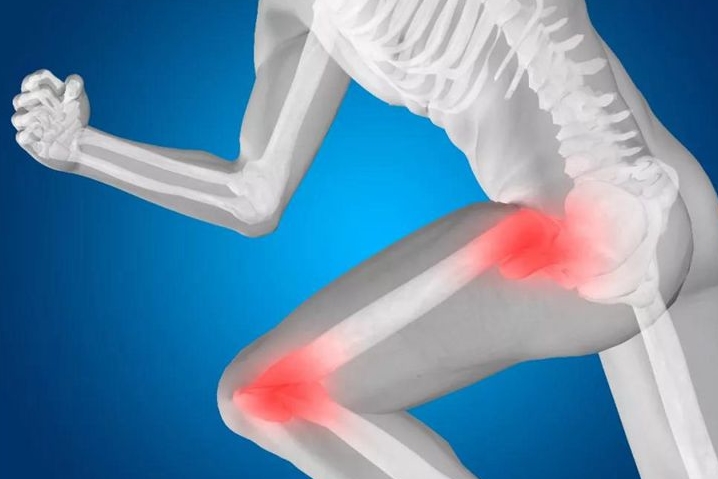

3363跑步伤膝盖?这件事更伤膝盖你却天天做

近年来不断有关于“日走万步伤膝盖”、“夜跑伤关节”的说法,很多人不敢过度运动,就怕伤了膝盖。美国《骨科与运动物理治疗杂志》曾发表一篇研究文章讲到:“健身跑的人们关节炎发生率仅3.5%,而选择静息生活方式、久坐不动人群的关节炎发生率却为10.2%,竞技体育的赛跑者的关节炎发生率13.3%”。结论是:久坐比跑步更伤膝。看到这个数据,是不是颇感意外?原来每天坐着刷微信,坐着看电视,坐着吃饭,坐着看报,坐...